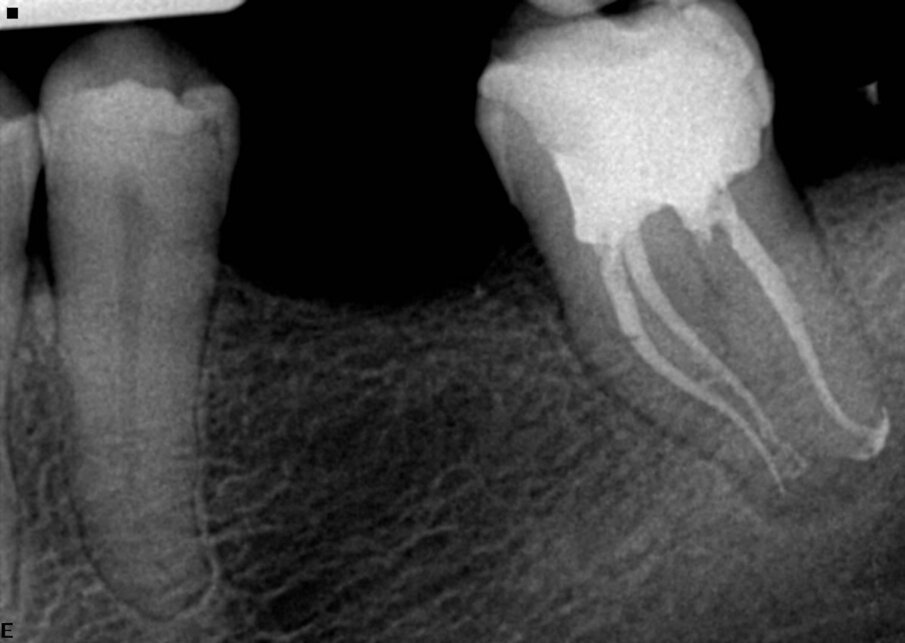

Drugi maksilarni molari su po mom mišljenju jedan od najzahtevnijih zuba za endodontsko lečenje zbog svog položaja i nepredvidive anatomije. U ovom primeru, pacijent je upućen zbog ireverzibilnog pulpitisa (Sl. 5). Gledajući preoperativni rendgenski snimak, možemo uočiti zakrivljenost posebno mezijalnih i palatinalnih kanala korena. Korišćena sekvenca je kao što je ranije opisano, počevši od otvarača 25/0.08 koliko god ide i to do tik iznad krivine, nakon čega sledi K-File 8 za određivanje radne dužine i 13/0.06 Traverse file koji se koristi za određivanje radne dužine u svim kanalima. Tokom korišćenja Traverse turpije 13/0.06 nisam osetio veliki otpor, pa sam odlučio da nastavim sa sekvencom konusa od 0.06. Sledeća turpija je bila 20/0.06 ZenFlex, a zatim 25/0.06 takođe ZenFlex. Lično, verujem u apikalno proširenje, i iz tog razloga sam koristio i ZenFlex  file 30/0.04 kao konačnu turpiju za proširenjee u ovom slučaju. Koristio sam srednji konus kao glavni i postigao 3D opturaciju sistema (Sl. 6). Naravno, izvršio sam kompletnu hemijsku pripremu, po svom redosledu, tokom postupka.